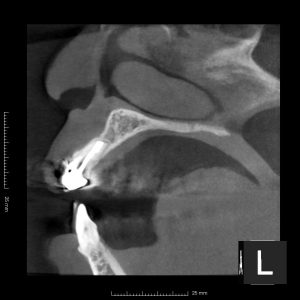

(術後1年のレントゲン、CT)

治療した3本とも、根尖部の骨は完全に再生しているのが確認できる。

術前にあった痛みの症状も、消失している。

患者さんも結果に満足しておられた。

マイクロスコープ下で行う歯根端切除術+逆根管治療は、90%という高い成功率を誇る。

症例によっては、今回のように歯根端切除術のみで対応できるケースもある。